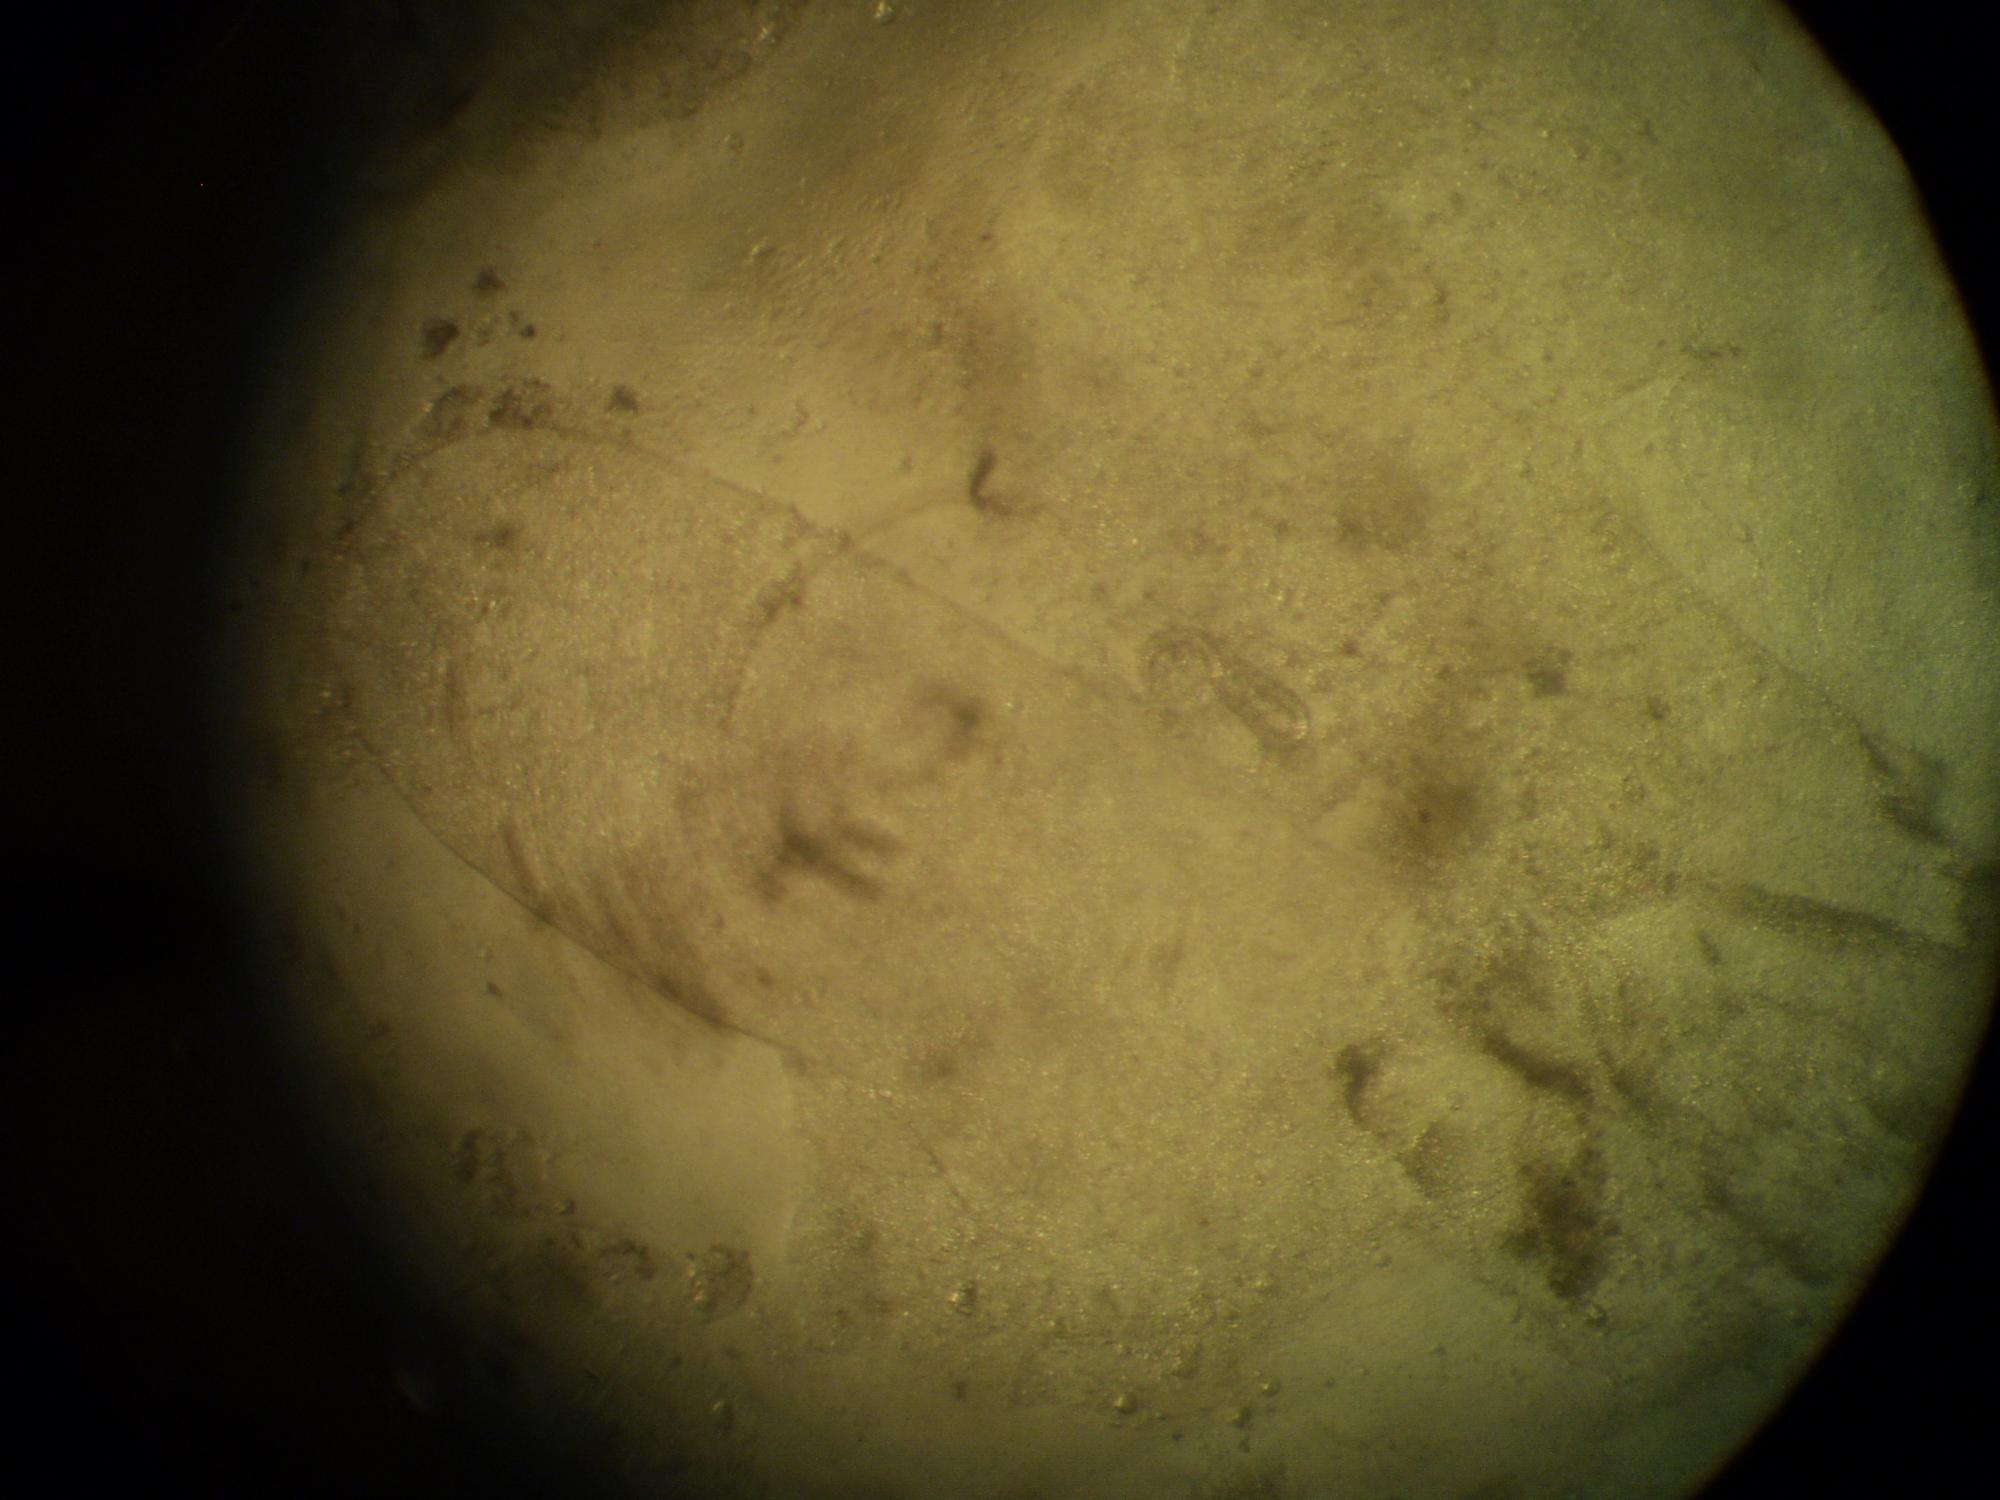

по центру

по центру в виде спиралей

по цетру изогнутая

в правом верхнем углу

Philometra

основные признаки болезни - похудание рыба.усохшая передняя часть спины.

лечение - пиперазин 1таб на 100гр корма.замочить мотыль или сухой корм на 20-30 минут..кормить один раз.следующий сеанс лечения не менее чем через 10-12 дней.

был вскрыт Red Pensil2

в теле найдено 3 нематоды.

рыбу скрывали у Юра Караванского.у него микроскоп отлично подходит для фотографирования.по мере возможности будут еще выставляться такие посты

если конечно надо

Вика.Р, забыл про это написать - печень.